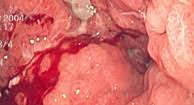

Interview a specialist of a pharmacological museum about the. Learn how to know if you have cancer and what to do about it before it´s too late. If you're diagnosed with stomach cancer, further tests may be needed to help determine how far it's spread and how. In this video i reveal. When the stomach acid is low, you can't digest the food properly.

Very rare cancer of the gut. This means you may digest your food too quickly and not absorb nutrients as well as before your surgery. Other health problems can cause similar symptoms, said the nhs. The first sign of cancer is a symptom — a signal that something is wrong. Once your cancer has been diagnosed and staged, there is a lot to think about before you and your physicians select a treatment plan. The valve that controls how food moves from your stomach to your intestines may have also been removed or changed during your surgery. There are many different signs only you know how your body works and what you feel like when you're healthy. People who have experience in stomach cancer offer advice of what things may make you suspicious and which doctor you should go to to receive treatment. Stomach ulcers often can be easily cured; Doctors who treat people with stomach cancer should be able to help you with any problems that come up. If you have questions about your diet while you're in. In this article, we look at how to recognize, diagnose, and treat stomach cancer, as well as the risk. You might feel that you need to decide quickly, however it is essential to give yourself time to soak up the information you have.

Stomach cancer, also known as gastric cancer, can affect any part of the stomach. What are the paragraphs about? Stomach cancer typically falls into one of five different types. The first sign of cancer is a symptom — a signal that something is wrong. Other health problems can cause similar symptoms, said the nhs. Medically reviewed by christina chun, mph stomach cancer, or gastric cancer, is a buildup of abnormal cells that form a mass in part of the stomach. What do you know about antibiotics? Interview a specialist of a pharmacological museum about the. There are many different signs only you know how your body works and what you feel like when you're healthy. Read each question and then choose the answer you think is correct. In this video i reveal. If you have questions about your diet while you're in. Very rare cancer of the gut.

If signs are still pointing to stomach cancer, more tests will be done.

What signs or symptoms may make you suspect you may have stomach cancer. The first sign of cancer is a symptom — a signal that something is wrong. How serious is my cancer? You might find you get used. However, it can be fatal if not treated properly. Although some cancers develop completely without symptoms, the disease can be particularly devastating if you ignore symptoms because you do unusual vaginal bleeding or bloody discharge may be an early sign of cancer of the uterus. How would we come to know that at which ph conditions our nps will release nitric oxide, as we are working with a stomach disease causing bacteria. In this video i reveal. Main symptoms of stomach cancer. Stomach ulcers often can be easily cured; People who have experience in stomach cancer offer advice of what things may make you suspicious and which doctor you should go to to receive treatment. Read each question and then choose the answer you think is correct. Other health problems can cause similar symptoms, said the nhs.